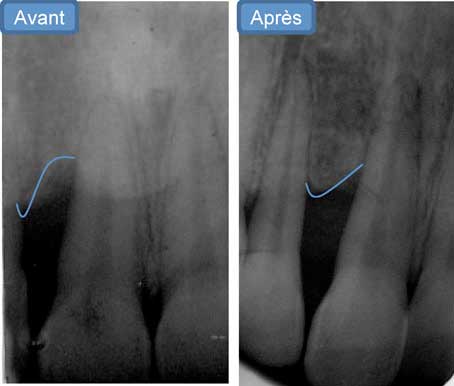

Contrôle après 9 mois :

Après 9 mois, on note une nette réduction des poches parodontales avec une valeur maximale de sondage de 3 mm.

Par contre on note une aggravation de la récession sur la 12 et la 11 (fig.7).

Sur le plan radiologique, on note une bonne cicatrisation osseuse entre la 11 et la 12 (fig. 8).

Vu le diabète que présente la patiente ainsi que le degré de lyse osseuse entre la 11 et la 12, la solution chirurgicale n’a pas été adoptée pour le traitement de cette récession.

Après concertation pluridisciplinaires entre parodontie / orthodontie / prothèse conjointe et après avoir eu le consentement de la patiente, notre attitude face à la récession et le diastème entre la 11 et la 12 était l’abstention.